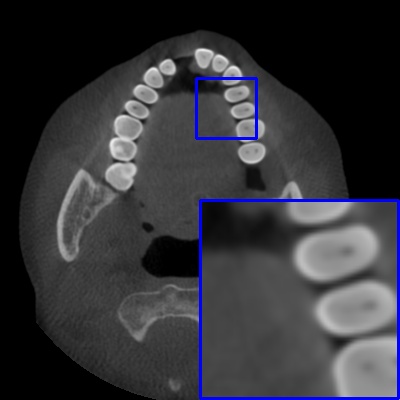

Figure 4: Comparison of MAR images by different methods on real-world MA image. The last image is the metal mask by selecting the pixel area over 2800HU in the MA image.

Results on real-world MAR. We also compare these methods on dental CBCT images with real-world metal artifacts. The visual results on one sample are shown in Fig. 4. We observe that our MARformer-T and MARformer-L well seperate the adjacent teeth and retain their shapes. This shows that our MARformers, though trained on synthetic data, are effective on real-world MAR.